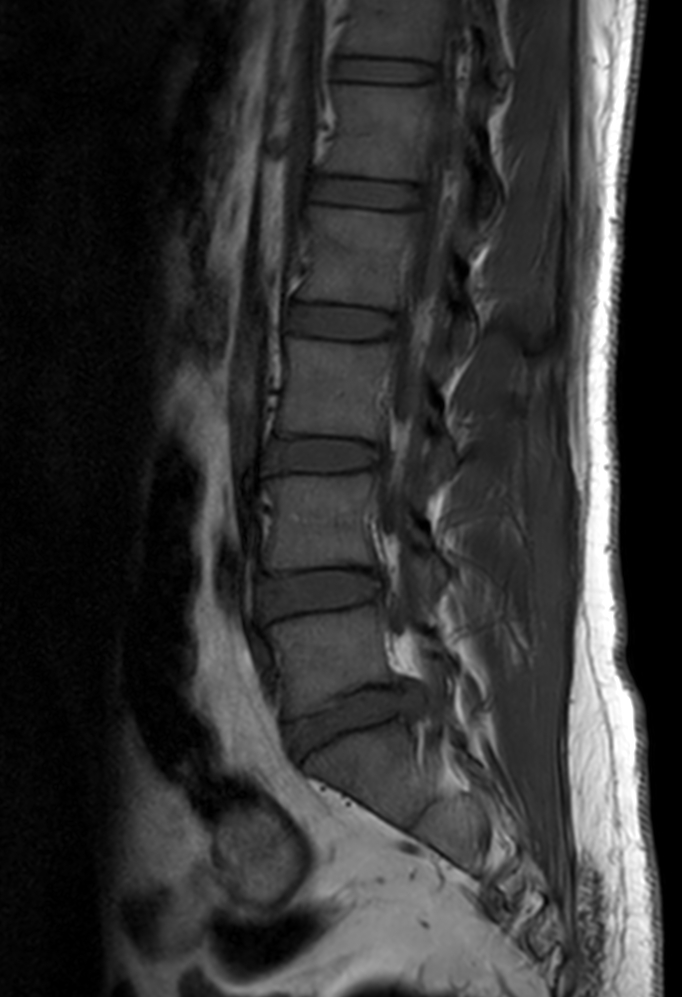

Lower back ache radiating to right lower limb. Diagnosis: Degenerative lower lumbar spondylosis, L5-S1 Stenosis

Sagittal T2w TSE